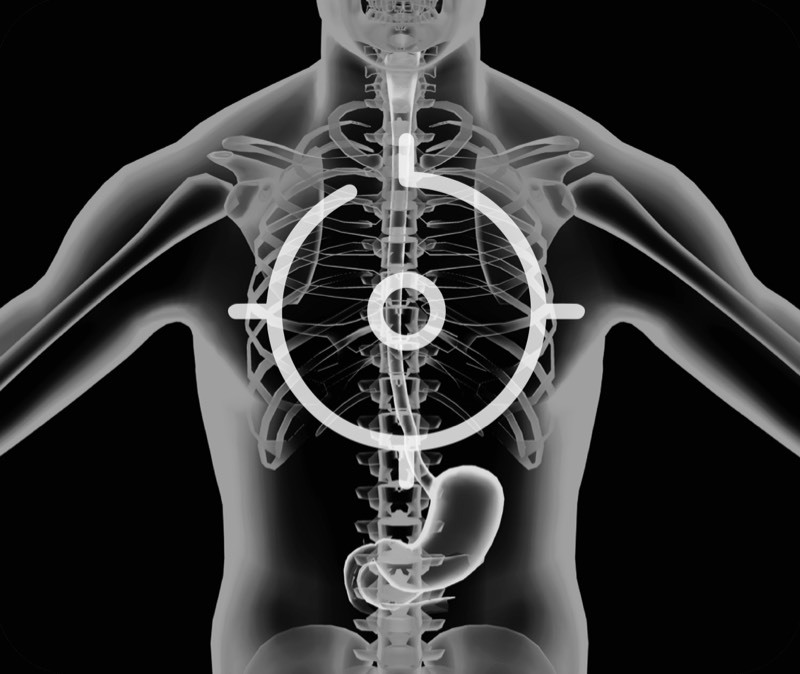

超声电子上消化道内窥镜

360°电子环形扫查与高清内镜影像相结合,提供了良好的插入性能和高清的内镜图像